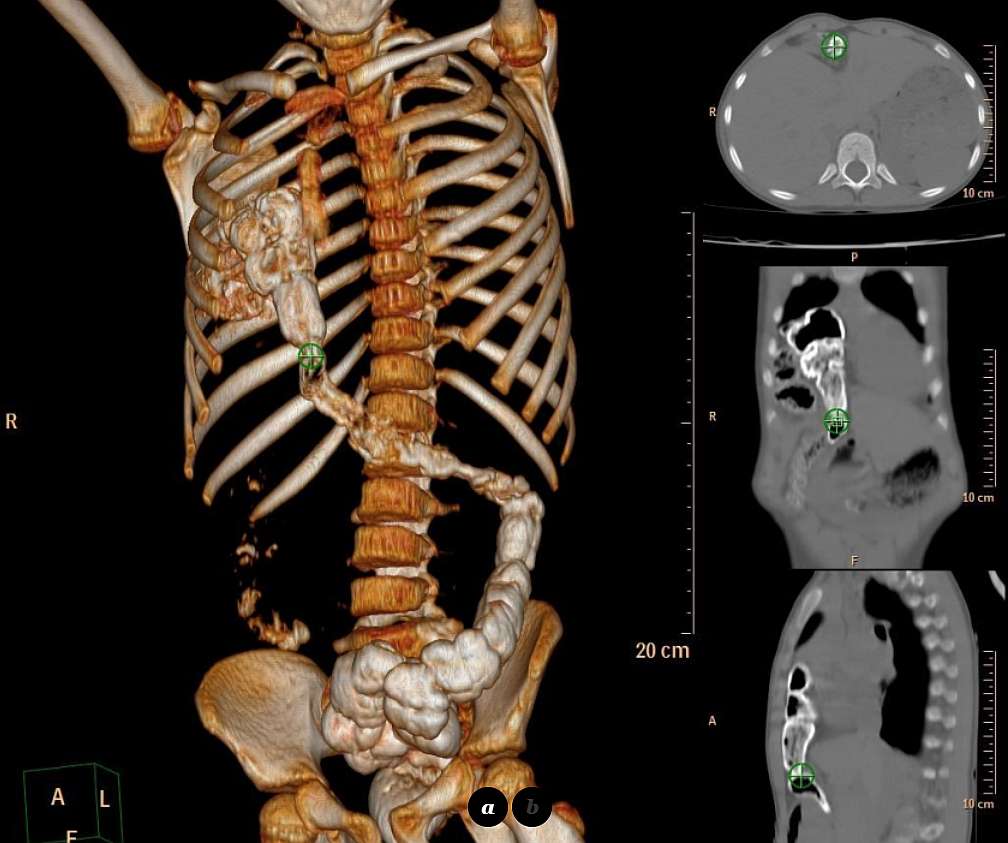

Computed tomography (CT) with multiplanar reconstruction (MPR), performed the following day showed a multilobulated heterogenous mass, with 9 cm at its maximal diameter, showing a regular thin border and entering (from the abdomen) the anterior and medial right hemithorax.

The mass was filled with oral contrast medium taken one day before, and lot of free air was shown within it as well. The hepatic flexure and most part of transverse colon – non-incarcerated – was herniated through the Morgagni foramen (image below). The diagnosis was confirmed surgically a few days later during surgical repair of the congenital defect.